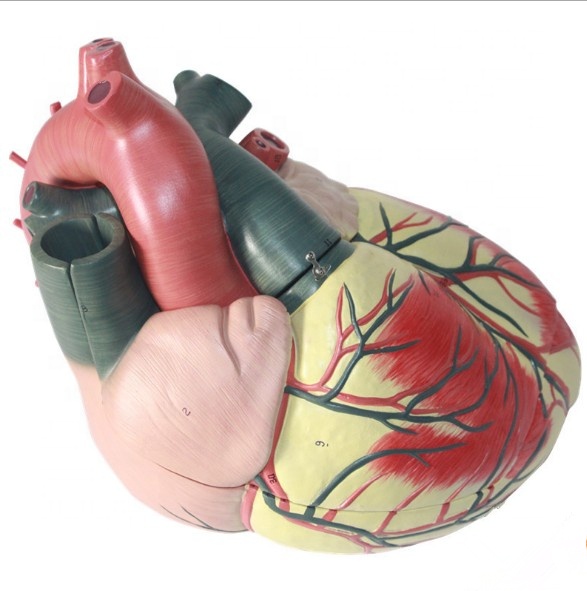

Фотографии и 3D-модели анатомии сердца человека